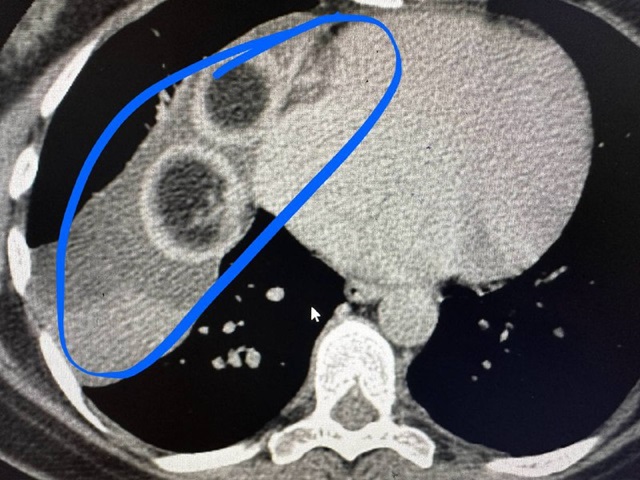

Врачи пояснили, что образование в средостении обнаружили у женщины на флюорографии. Компьютерная томография подтвердила диагноз.

Оказалось, что рядом с сердцем выросла дермоидная киста размером 10 на 7 на 15 сантиметров. Внутри этой кисты обрадовались две большие волосяные головки.